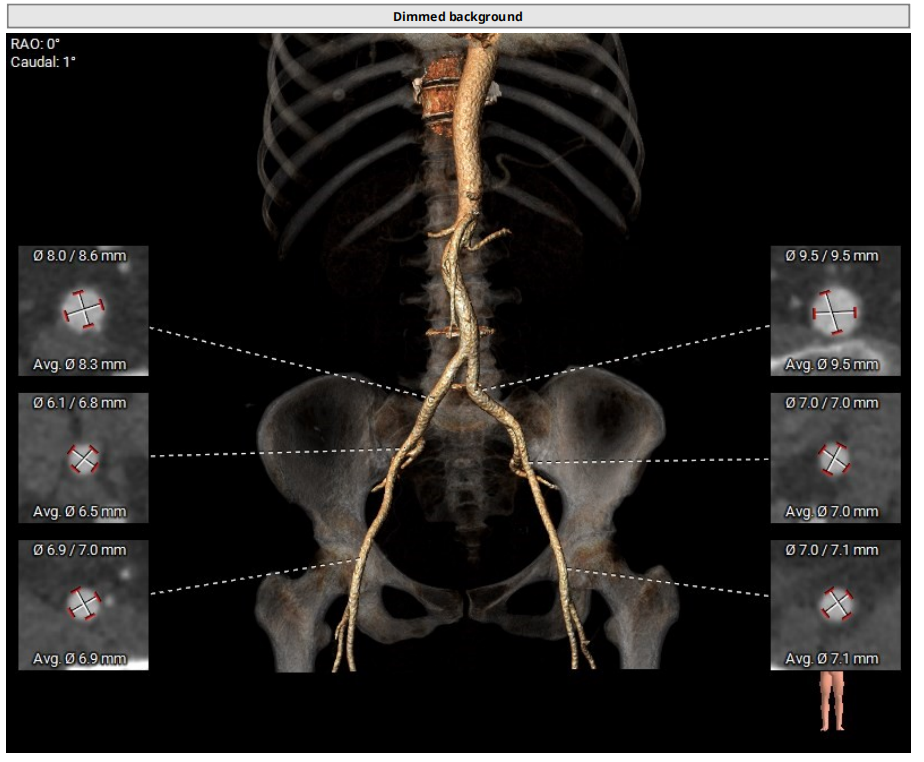

外周入路分析

外周入路血管条件良好,内径可,无明显钙化;主动脉弓降主动脉出有明显狭窄和弯折,弓缩窄最窄处13mm,输送系统过弓可能有明显的困难,替代选择可以考虑颈动脉入路或者上长鞘拉直弯折。